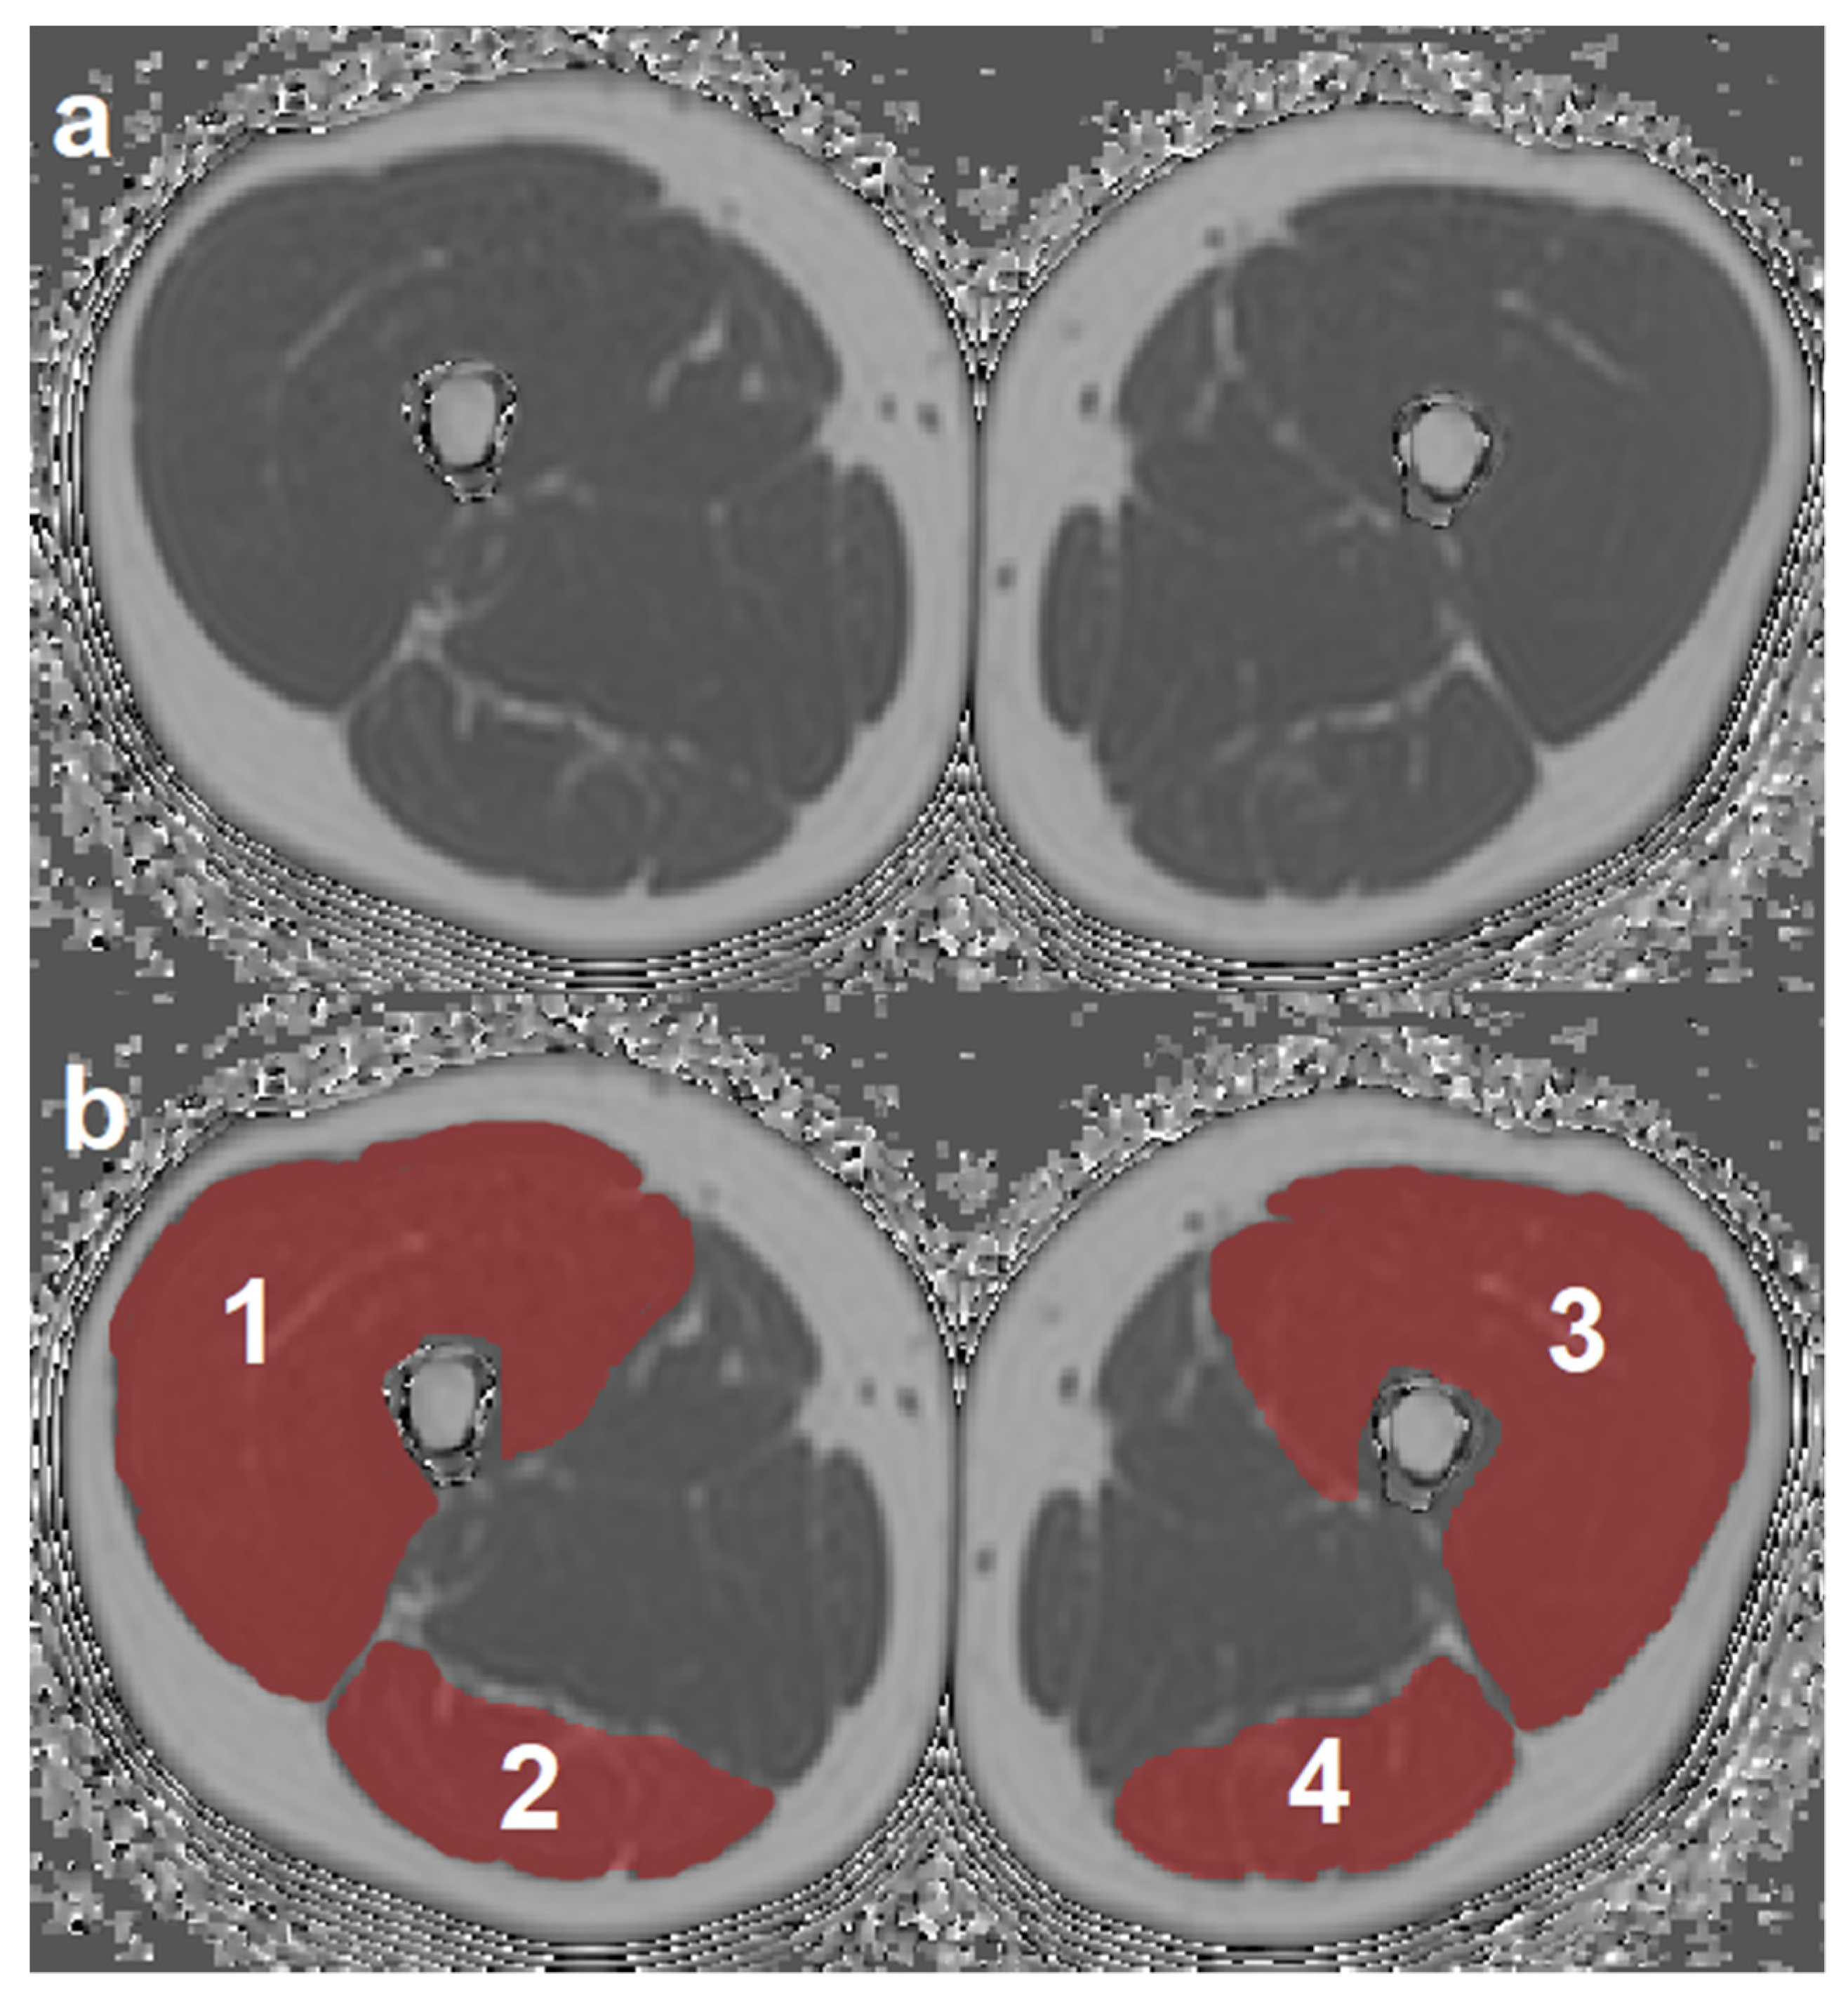

2.3. MR Image Segmentation

2.4. Texture Analysis of PDFF Maps